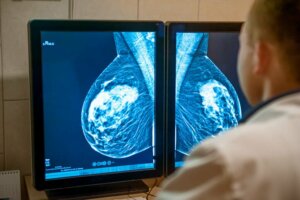

La stadification peut être à la fois clinique et pathologique. La forme clinique est faite sur la base des différentes imageries et biopsies réalisées. De son côté, la détermination pathologique n’est possible qu’après chirurgie, au cours de laquelle un spécialiste analysera le tissu extrait.

Au cours de ces étapes, l’une des méthodes de diagnostic préférées sont les tests d’imagerie tels que la mammographie et l’échosonogramme du sein. Le pronostic est également généralement bon dans la plupart des cas, en fonction de la présence de récepteurs hormonaux et de la production de protéine HER2.